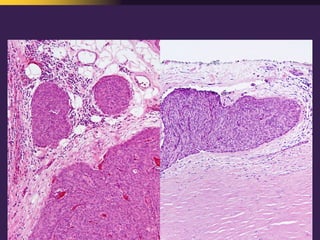

This document discusses mediastinal pathology using a compartmental approach. It describes the anatomy of the mediastinum and divides it into anterior, middle, and posterior compartments. Each compartment contains different structures and has a characteristic distribution of lesions. For example, 50% of lesions occur in the anterior compartment, which contains the thymus. The thymus is the most common site of lesions in the anterior compartment. Thymomas are the most common epithelial tumors of the thymus and mediastinum.